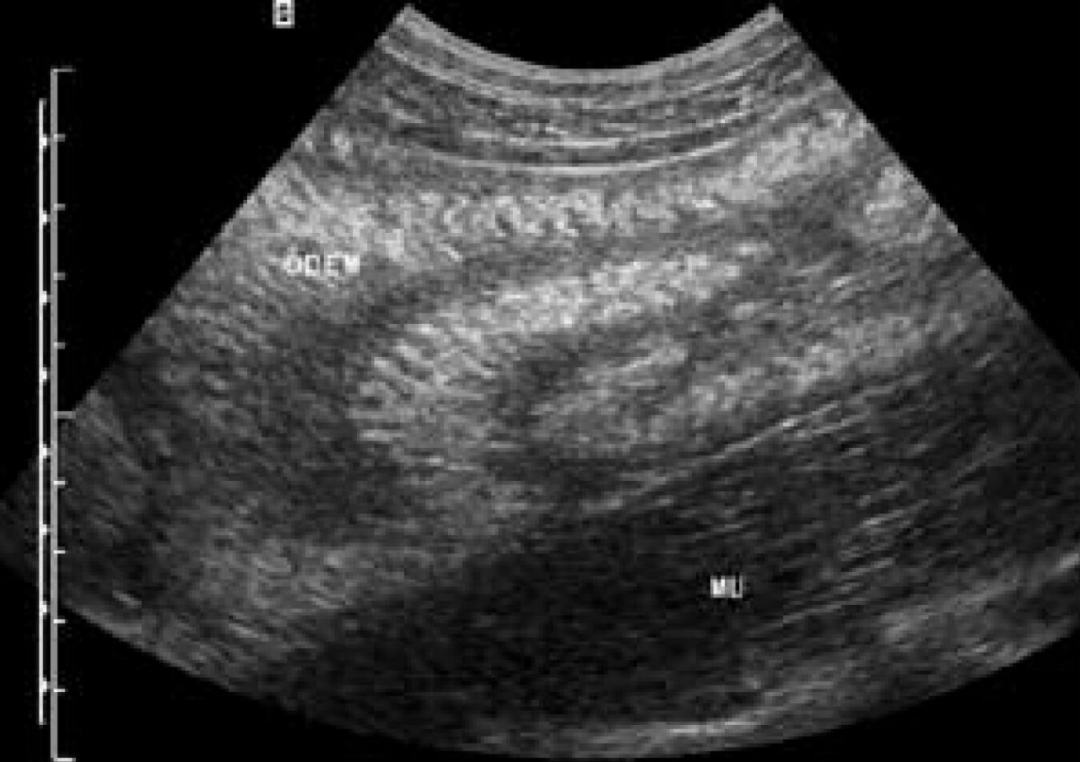

通常我们所遇到的肠道炎症或肿瘤,往往会带来低回声增厚的肠壁,而今天我们所要见到的是“白色”高回声增厚肠壁,这您听说过吗? 图1-2:分枝杆菌所致“白肠”。病例1,患者,37岁,男性,AIDS合并鸟